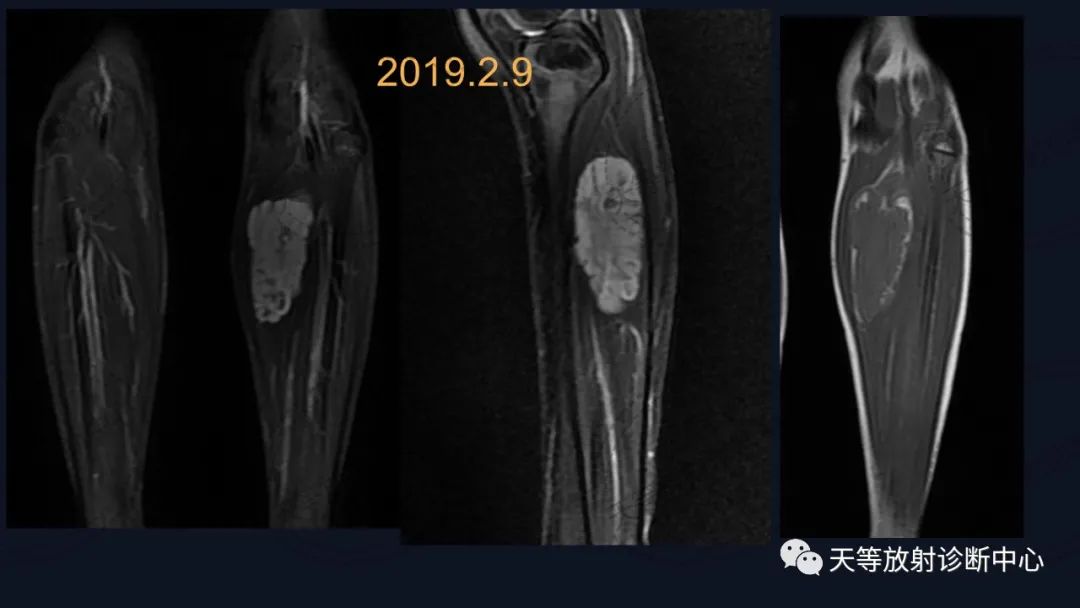

上图:压脂序列肿块椭圆形,内部见细小分隔,血管流空信号。

T1WI肿块边缘见环状高信号影,考虑出血信号。

前后两次对比观察,病灶略有增大。